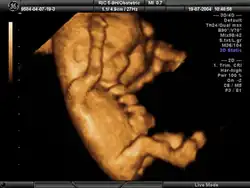

Ecografía obstétrica

La ecografía obstétrica[1]es un procedimiento de carácter médico usado para determinar la existencia de un embarazo y conocer las condiciones del embrión o feto, así como de la placenta, útero, cuello del útero y líquido amniótico. La ecografía es un procedimiento de diagnóstico que emplea el ultrasonido compuesto para crear imágenes bidimensionales o tridimensionales. Un pequeño instrumento (muy similar a un micrófono) llamado transductor emite ondas de ultrasonidos. Estas ondas sonoras de alta frecuencia se transmiten hacia la parte del cuerpo en cuestión (en este caso, el vientre) y se recibe su eco, el cual es procesado por un ordenador que muestra una imagen del feto sobre el que ha incidido el ultrasonido.

Esta técnica se considera el método más seguro para conocer el estado general del embarazo y, según las semanas de gestación, tiene sus indicaciones específicas. El examen se lleva a cabo a través de imágenes. Las ondas sonoras reflejadas en el interior del vientre materno permiten ver el desarrollo del feto. También se usa para ver los órganos pélvicos de la madre durante el embarazo. La ecografía obstétrica no emplea radiación ionizante.